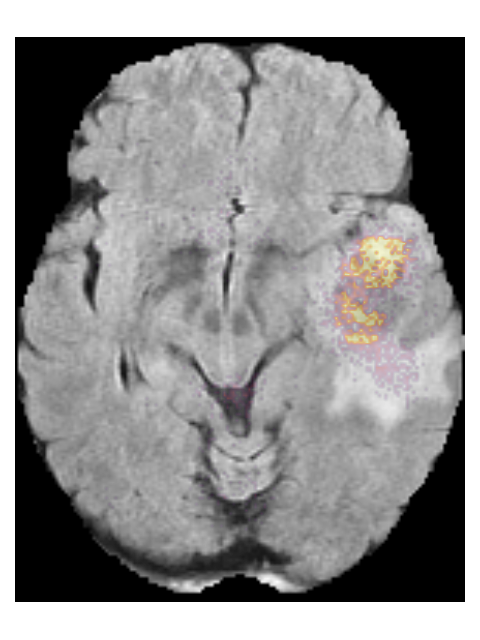

To provide insight into the behavior of our model we created saliency maps, which show which parts of the scans contributed the most to the prediction. These saliency maps are shown in Figure 6 for two example patients from the test set. It can be seen that for the LGG the network focused on a bright rim in the T2w-FLAIR scan, whereas for the HGG it focused on the enhancement in the post-contrast T1w scan. To aid further interpretation, we provide visualizations of selected filter outputs in the network in Appendix D, which also show that the network focuses on the tumor, and these filters seem to recognize specific imaging features such as the contrast enhancement and T2w-FLAIR brightness.